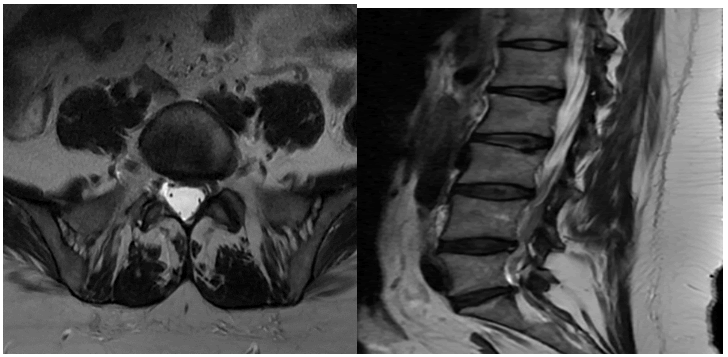

Journal-Neurological-Disorders-Spine

Figure 3. MRI lumbar spine T2 sagittal and axial view of the same patient shows no interval changes after 3 years with good outcome improvement of both lower back pain and leg pain.

Journal-Neurological-Disorders-Cervical

Figure 4. MRI cervical spine coronal and axial cuts of a male patient presented by right radicular pain with slight neck pain shows: Straightening of cervical lordosis, C6/C7 right paracentral moderate disc protrusion with compression of the right C6 nerve root and narrowing of the right neuroforamen.